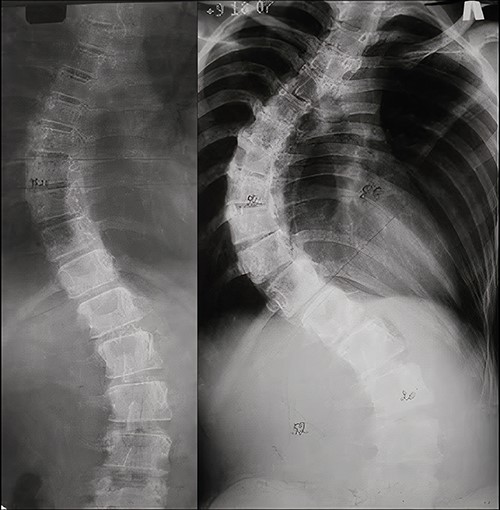

Due to rapid deformity progression and incomplete skeletal maturity, 2-stage surgical treatment was elected. At the first stage, posterior correction and T1-L5 instrumentation using the LSZ growing system were performed. The intervention lasted 125 min. Blood loss amounted to 240 ml. The postoperative period was uneventful. Radiographs on postoperative Day 5 demonstrated 83% correction (Fig. 3a). The immediate postoperative sitting height was 75 cm.

Radiographic results of surgical treatment. (a) AP X-rays of the patient’s spine in standing position after the 1st stage of surgical treatment on the 5th day after surgery. Residual deformity of the spine was 15°. (b) AP X-ray of the patient’s spine in a standing position 4 years after surgery. Growth of the spine and the associated shortening of the free upper and lower ends of the plates can be observed (red arrows). (c) AP X-ray of the patient’s spine after the 2nd stage of surgical treatment. The angle of residual deformity is < 5°.

At a 4-year follow-up at the age of 16, the spine grew by 5 cm. The patient’s sitting height was 80 cm. Shortening of the free ends of the plates at the upper and lower ends of instrumentation, associated with the continued growth of the spine could be clearly visualized (Fig. 3b).

As the second stage of surgical treatment, the LSZ system was removed and definitive T4-T12 instrumentation was performed. The duration of the surgery was 203 min. Blood loss amounted to 450 ml. Postoperative radiographs demonstrated 94% deformity correction (compared with deformity before index surgery) (Fig. 3c). The patient was mobilized on Day 2.